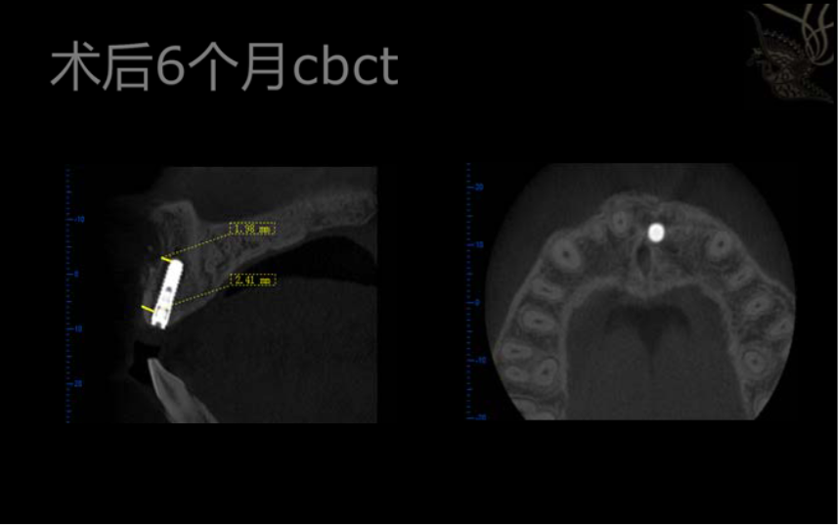

術(shù)后CBCT,植體位置達到術(shù)前預期

術(shù)后6個月CBCT,頰側(cè)無明顯骨吸收,骨結(jié)合良好